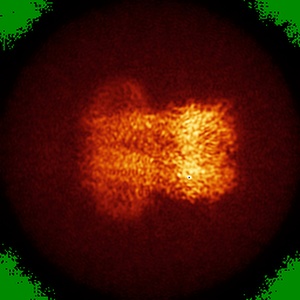

Cyro-EM structure of human Glycine Receptor alpha2-beta heteromer, glycine bound, (semi)open state

Sample: Glycine receptor alpha2-beta heteromer, glycine bound, open state

Characterization of the subunit composition and structure of adult human glycine receptors

Yu H, Bai X-C, Wang W

(2021) Neuron , 109 , 2707 - 2716